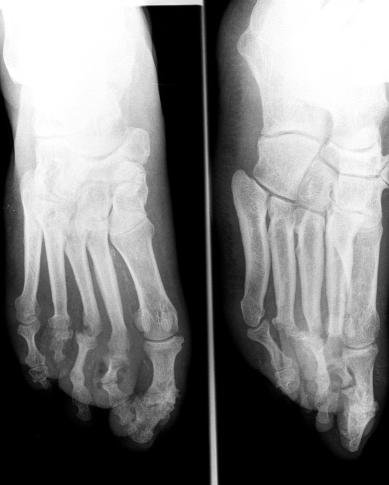

Radiografía de pie diabetico

Alteraciones en tejido óseo

• Infección ósea (osteomielitis)

• Cambios articulares y óseos neurotróficos, con atrofia, reabsorción y necrosis ósea eventualmente.

• Osteopatía diabética

• Neuroartropatia

Osteopatía diabética. Deformación y atrofia

RX pie diabetico. Degeneracion ósea en ante pie inferior

En la historia natural del pie diabético y formación del callo óseo intervienen, la insensibilidad del paciente a los microtraumatismos, la mala cicatrización de las heridas, la  alteración de la biomecánica del pie y la fricción en zonas concretas por la deformidad del pie, junto con el calzado inadecuado. La permanencia de ésta situación da lugar a la hipertrofia de la piel, pero esta hipertrofia no protege de la infección. Las deformidades, propiciadas por la atrofia y la neuropatía, las alteraciones articulares y el daño de tendones y ligamentos, determinan la localización del callo y la erosión cutánea:

ANTEPIE: la zona más frecuente de formación del callo es en la cabeza del 2º metatarsiano, pero también el la superficie plantar de las cabezas de los otros metatarsianos.

MEDIOPIE: se produce la deformidad “en mecedora” pudiendo formarse callo y úlcera en la superficie plantar del cuboides y en la cara dorsal de las bases de los metatarsianos subluxados.

RETROPIE: en la superficie plantar del aspecto posterior del calcáneo, en los maleolos. La ruptura del callo da lugar a la ulceración focal.

Por lo tanto, las úlceras se localizan en las áreas de mayor presión durante la deambulación y los microtraumatismos repetidos, siendo más prevalentes en las cabezas de primero y quinto metatarsianos, superficie plantar del segundo y tercer metatarsiano y superficie dorsal de los dedos; en el retropie, en el aspecto posterior del calcáneo y en el maleolo medial y lateral.